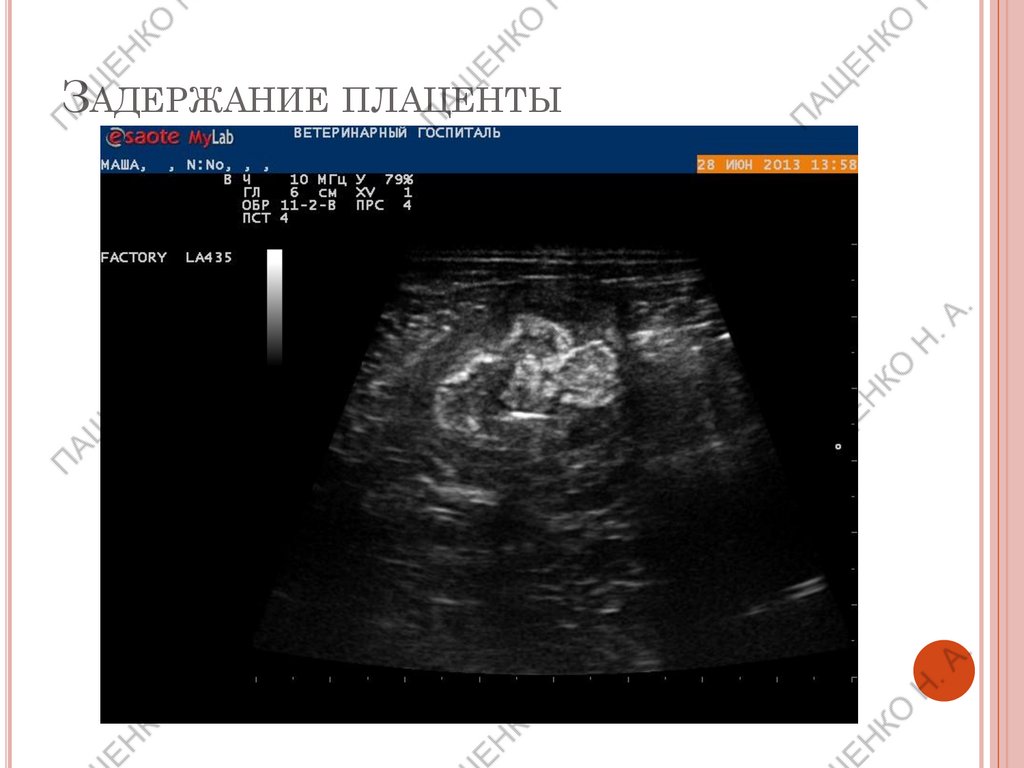

ЗАДЕРЖАНИЕ ПЛАЦЕНТЫ